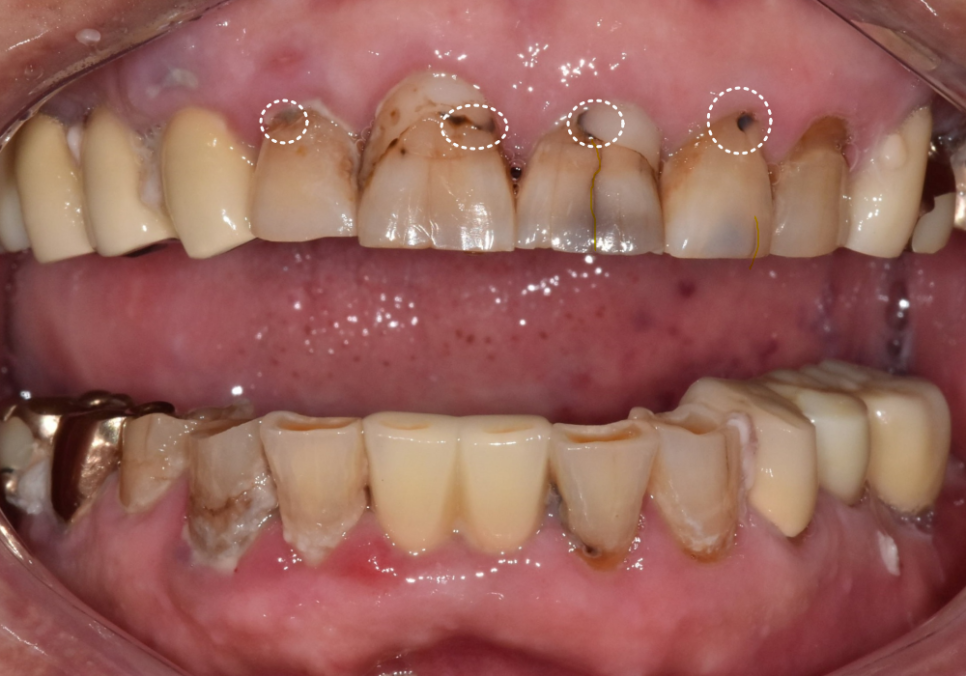

최근 내원하신 환자분은

앞니 사이 음식물 끼임이 심해지면서

치아가 검게 변색된 상태였어요.

육안으로도 깊은 충치가 보였고,

과거에 레진으로 치료했던 부위 안쪽으로

2차 충치가 진행되고 있었죠.

위의 앞니에 금도 가있네요.

이번에 문제가 생긴 앞니들은

신경치료 후 보철물을 연결하는

스플린트 형태로 제작하기로 계획했습니다.

치료 계획

#12~23 신경치료 및 지르코니아 스플린트

#42, 43, 44 및 #32, 33 신경치료

및 지르코니아 스플린트

3)진행 방식

연세를 고려하여 상악부터 순차적으로 천천히 진행